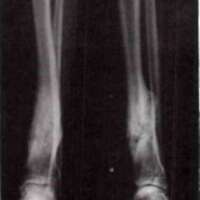

P.S. was born on February 28, 1953. He suffered from congenital pseudarthrosis of the right tibia and fibula, essentially constituting a defect similar to an ununited fracture. Prior to referral to the Crippled Children's Service Clinic in Birmingham, he had undergone surgery at an early age. This surgery, involving the use of metallic screws and sutures, was unsuccessful. Further surgical procedures were attempted subsequently, an onlay bone graft being done on July 20, 1965. This surgery was followed by infection and was unsuccessful. A sliding bone graft was attempted on June 6, 1967, but this also was unsuccessful.

The VAPC PTB brace was fitted in April 1968. The condition of the right tibial and fibular defects at that time is shown in Fig. 4. The brace prescription included a SACH heel and a rocker bar incorporated into the shoe build-up (the right leg being shorter than the left). Initially, no motion was provided at the ankle joint.

Although the patient was well pleased with the brace and wore it satisfactorily, the tibial and fibular defects failed to unite (Fig. 5).